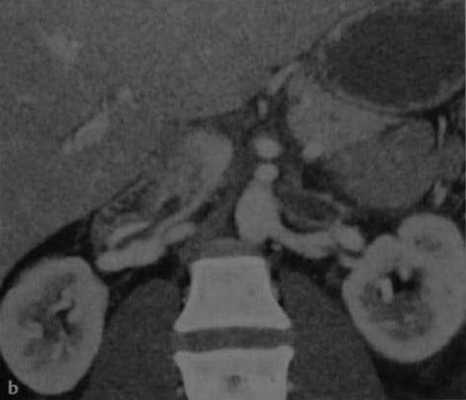

Двусторонний тромбоз почечных вен в послеродовом периоде. (a) Аксиальная МСКТ после контрастного усиления. Расширенная левая почечная вена с дефектом заполнения в просвете;

(b) Фронтальная МСКТ. Распространение тромба из правой почечной вены в нижнюю полую.